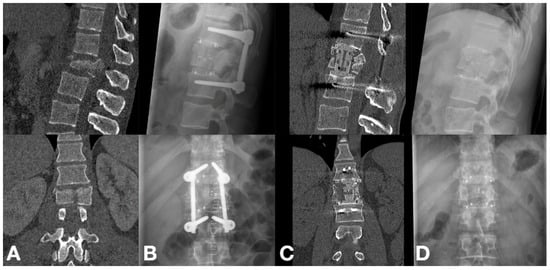

3.2. Radiographic Outcomes

3.3. Clinical Outcomes